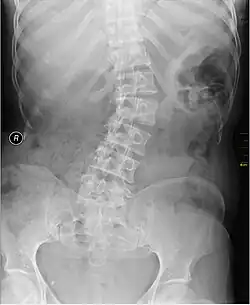

| Kyphosis (left) and scoliosis (right) depicting iliocostal contact (a) | |